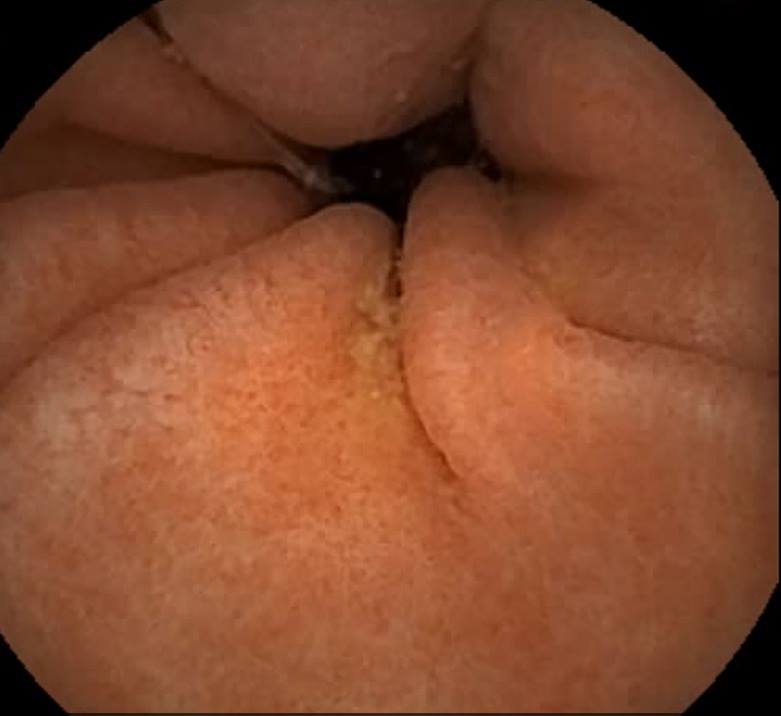

Capsule Endoscopy: A Normal Pylorus